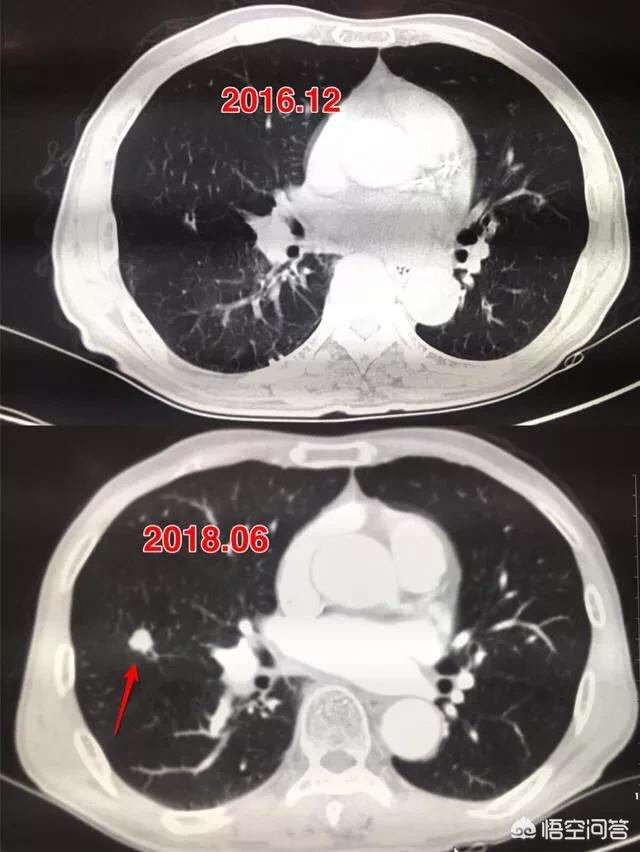

Ein kleiner solider Knoten wie dieser, etwa 4 mm, war glatt und zeigte keine offensichtlichen Anzeichen von Bösartigkeit. Aber zwei Jahre und vier Monate später:

Die Pathologie bestätigte später, dass es sich um einen kleinzelligen Lungenkrebs handelte.

Der Pfeil zeigt auf den Knoten, der sehr klein war, als er im März 2016 entdeckt wurde, etwa 0,5 cm, und jetzt werden bei Routineuntersuchungen sehr viele Knoten wie dieser entdeckt.Es gibt keine Möglichkeit, auf den Bildern festzustellen, ob es gut- oder bösartig ist, sondern nur die Möglichkeit der Überprüfung, und die Überprüfung und Nachsorge ist auch das beste Mittel.

Sieben Monate später, bei der zweiten Nachuntersuchung im Oktober 2016, wurde deutlich, dass dieser Knoten größer und runder geworden war. Der vergrößerte Knoten bei der Nachuntersuchung sollte auf die Möglichkeit einer Bösartigkeit hinweisen, aber dieser Patient entschied sich dennoch nicht für eine Operation.

Nach weiteren 1 Jahr und 2 Monaten, die dritte Überprüfung im Dezember 2017.Sie können sehen, dass dieser Knoten ist viel größer als zuvor, die bösartigen Zeichen sind lobulierte aus und es hat sich im Inneren fest, diese Zeichen diagnostizieren die Lunge Krebs im Grunde, aber der Patient immer noch nicht haben Chirurgie.